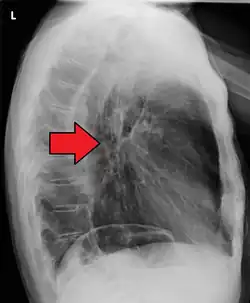

Although an occlusive tumor may be suspected on a barium swallow or barium meal, the diagnosis is best made with an examination using an endoscope. This involves the passing of a flexible tube with a light and camera down the esophagus and examining the wall, and is called an esophagogastroduodenoscopy. Biopsies taken of suspicious lesions are then examined histologically for signs of malignancy.

Additional testing is needed to assess how much the cancer has spread (see § Staging, below). Computed tomography (CT) of the chest, abdomen and pelvis can evaluate whether the cancer has spread to adjacent tissues or distant organs (especially liver and lymph nodes). The sensitivity of a CT scan is limited by its ability to detect masses (e.g. enlarged lymph nodes or involved organs) generally larger than 1 cm.[44][45] Positron emission tomography is also used to estimate the extent of the disease and is regarded as more precise than CT alone.[46] PET/MR as a novel modality has shown promising results in preoperative staging with fair feasibility and good correlation in comparison to PET/CT. It can enhance tissue differentiation with lowering the radiation dose to the patient.[47] Esophageal endoscopic ultrasound can provide staging information regarding the level of tumor invasion, and possible spread to regional lymph nodes.

Contrast CT scan showing an esophageal tumor (axial view)

Contrast CT scan showing an esophageal tumor (coronal view)